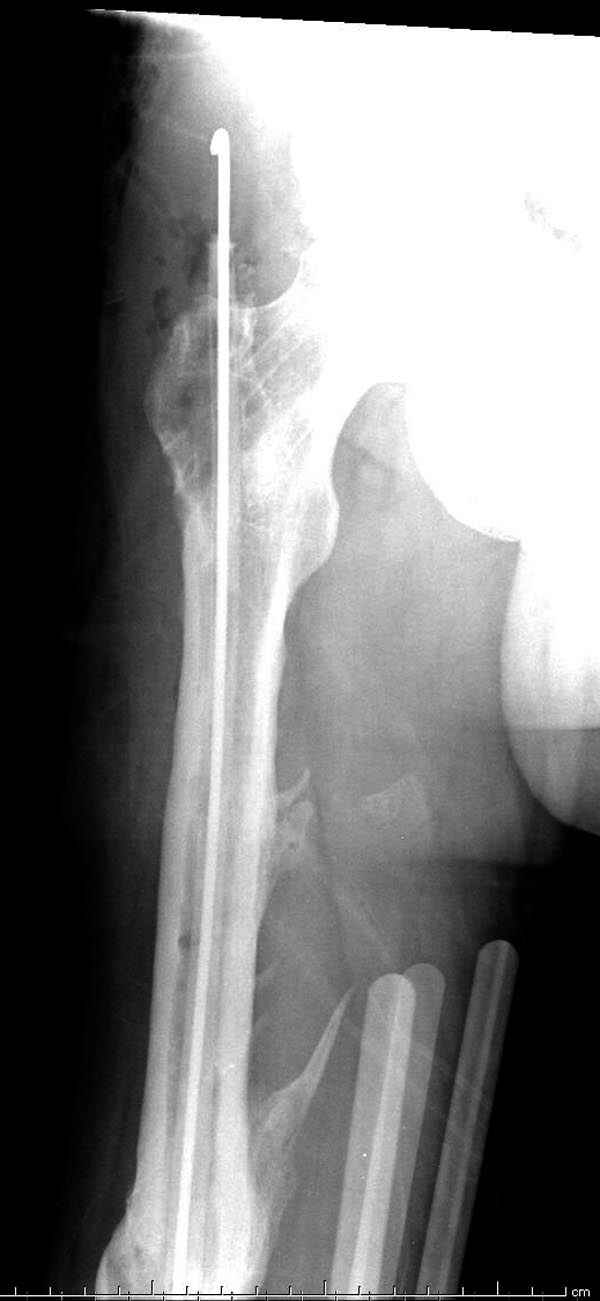

Представляю снимки больного с политравмой: леченного в другом мед.учреждении по поводу открытого перелома бедра, сперва аппаратом наружной фиксации, затем пластиной. Обратился к нам через 8 месяцев после удаления пластины с проблемой несросщего перелома бедренной кости, без клинических проявлении к инфицированию (не все снимки сохранены)

Рутинный интрамедуллярный остеосинтез с расверливанием и с фиксацией реконструктивным трокантерик штифтом (рис №1, №2),

если первые 4 месяца послеоперационного периода проходил без проблем, но на 5 месяце появились боли в дистальном отделе бедра и температура, т.е. симптомы медуллярного инфицирования (рис №3, №4).